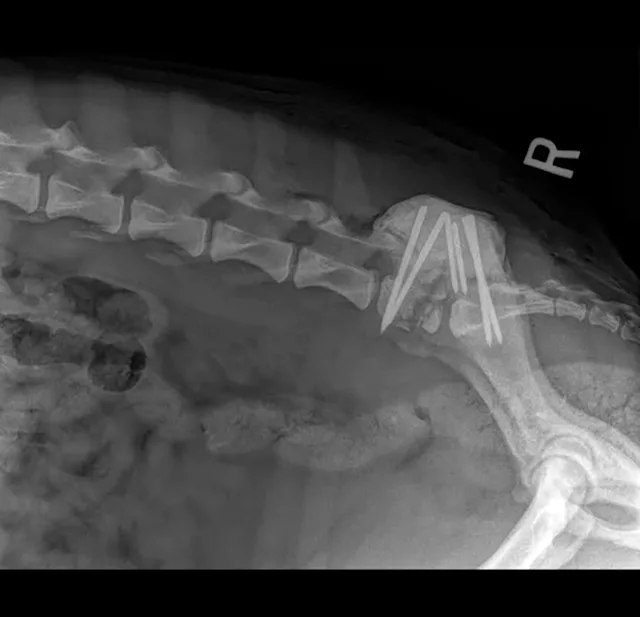

Patients with moderate-to-severe lumbosacral disease that causes pain unresponsive to medical management and patients with neurologic abnormalities should be considered surgical candidates. The main goal of surgery is decompression of the cauda equina, which can relieve the patient’s pain. Dorsal laminectomy with or without foraminotomy is most often performed.1,5,9,11

Distraction and stabilization may be required to correct ventral subluxation of S1, prevent further lumbosacral instability, or decompress the L7 spinal nerve in the intervertebral foramen. In a single study, an average of 78% of dogs undergoing surgery had an excellent or good outcome, as assessed by both owners and veterinarians.12 Careful preoperative consideration is recommended for patients with urinary and/or fecal incontinence, as surgical resolution of incontinence can be poor. The same study documented that the presence of urinary and/or fecal incontinence before surgery is the only individual clinical sign that significantly affects outcome.12,13